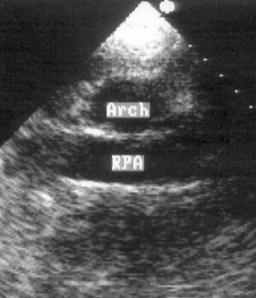

Супрастернальная позиция длинной оси дуги аорты, супрастернальная позиция короткой оси дуги аорты (рис. 2.21, 2.22)

Супрастернальный доступ позволяет исследовать крупные сосуды: грудную аорту и ее ветви, легочную артерию, верхнюю полую вену. У взрослых пациентов эта позиция используется главным образом для допплеровских исследований. Датчик устанавливается в яремную ямку, голова пациента должна быть повернута в сторону примерно на 45°. Центральный ультразвуковой луч направляют вниз. Плоскость датчика поворачивают таким образом, чтобы регистрировалась максимальная ширина дуги аорты на всем ее протяжении. На изображении дуга аорты находится вверху, нисходящий отдел аорты занимает правый край изображения, восходящий — левый. У многих пациентов нисходящий и восходящий отделы аорты не помещаются на изображении одновременно, в таких случаях следует переместить датчик вправо для визуализации восходящей аорты или влево для визуализации нисходящей аорты. Справа вверху на изображении можно видеть левую сонную артерию, ниже — левую подключичную артерию. Под дугой аорты, в середине изображения находится правая легочная артерия. Повернув датчик на 90°, можно получить супрастернальную позицию короткой оси дуги аорты. В этой позиции в изображение попадают дуга аорты по короткой ее оси и правая легочная артерия по ее длинной оси.

Рисунок 2.22. Супрастернальная позиция короткой оси дуги аорты. Arch — дуга аорты, RPA — правая легочная артерия.